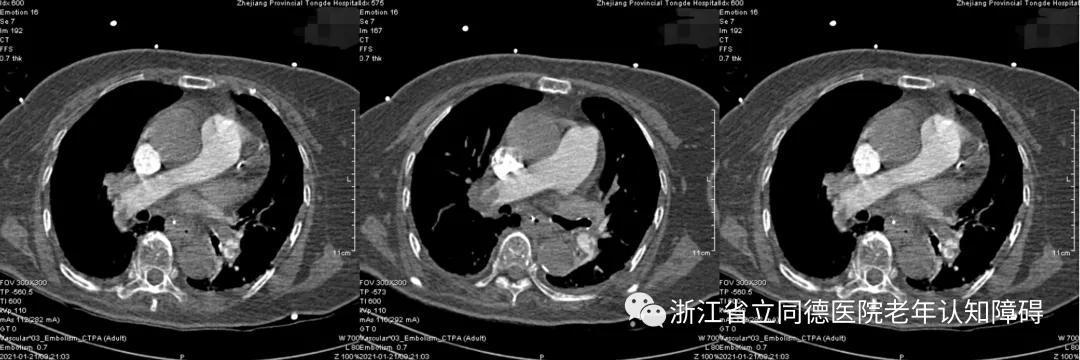

然而,高奶奶的特殊疾病经历使医生对选择抗精神病药物却有了顾虑:原来在此之前1个多月左右高奶奶因呼吸急促、氧饱和度下降曾在重症监护病房(ICU)闯过鬼门关,当时高奶奶的血液检测: 氧合指数仅100mmHg,D-二聚体>30mg/L ,胸部CTA检查提示左右肺动脉主干及多发分支栓塞,确诊“ 肺动脉栓塞 ”,病情十分危重,经过抗凝、呼吸机辅助治疗,高奶奶“肺栓塞”病情好转。

肺CT:肺栓塞